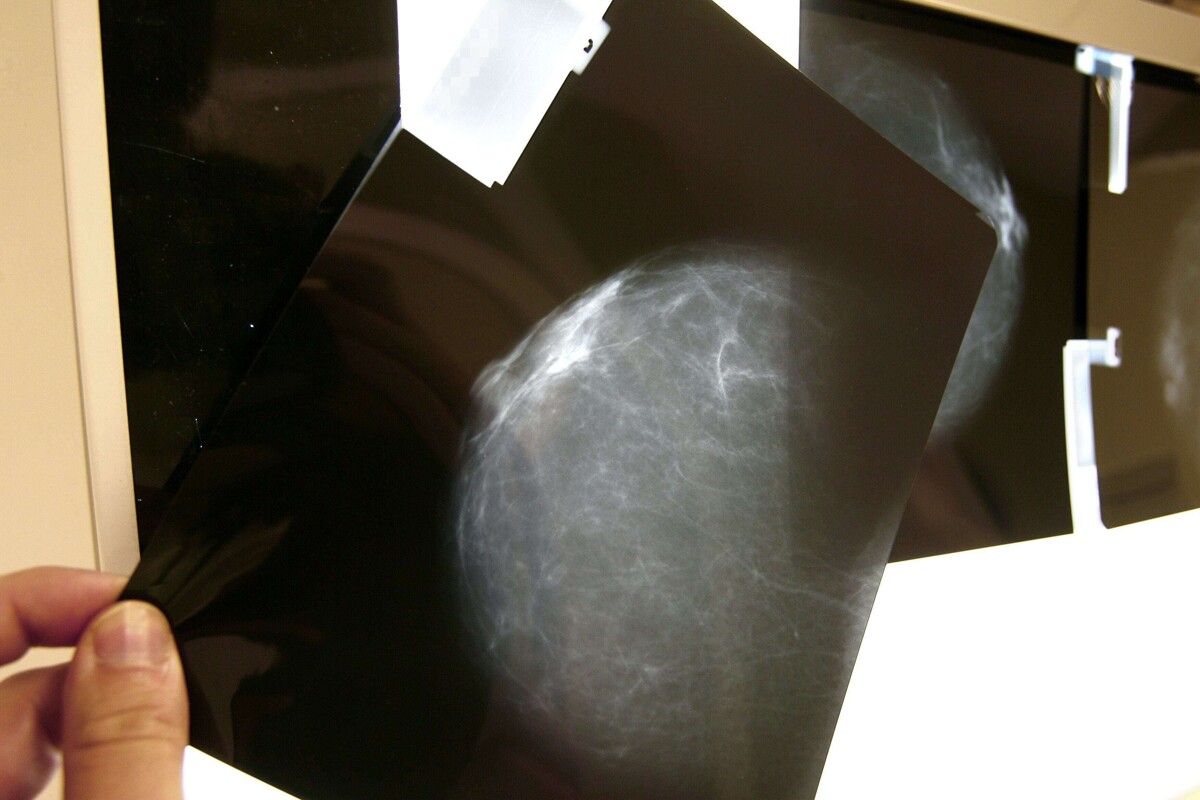

Un alto porcentaje de casos de cáncer de mama en México se detecta en mujeres menores de 40 años. La falta de protocolos de diagnóstico temprano lleva a detecciones en etapas avanzadas y menor probabilidad de curación. La Fundación Alba lanzó una campaña para concientizar.

El cáncer de mama en mujeres jóvenes encendió alertas en México, luego de que especialistas señalaran que una proporción significativa de casos se detecta en menores de 40 años, sin protocolos adecuados de diagnóstico temprano. Miryana Pérez Vela, directora de Fundación de Alba, explicó en entrevista con Publimetro que entre el 11% y el 15% de los diagnósticos anuales de cáncer de mama en el país corresponden a mujeres menores de 40 años. Este porcentaje, detalló, es superior al registrado en otros países, donde la incidencia en este grupo suele oscilar entre el 7% y el 9%, lo que coloca a México en una situación atípica. Falta de protocolos retrasa diagnósticos. Uno de los principales problemas, señaló Pérez Vela, es que no existen guías clínicas específicas para la detección de cáncer de mama en mujeres jóvenes. Esto provoca que muchas pacientes no sean sometidas a estudios como mastografías o ultrasonidos en etapas tempranas, lo que deriva en diagnósticos avanzados y menor probabilidad de curación. “Llegan en etapas avanzadas, lo que reduce el pronóstico y la calidad de vida”, advirtió. Factores de riesgo y mitos sobre la edad. La directora de la fundación subrayó que uno de los principales mitos es considerar que la edad es un factor protector, cuando en realidad el primer riesgo es ser mujer. Además, explicó que entre el 15% y el 20% de los casos podrían estar relacionados con factores genéticos, aunque también existen pacientes sin antecedentes familiares. Campaña busca detección temprana. Ante este panorama, Fundación de Alba lanzó la campaña “Está en tus manos”, enfocada en promover la autoexploración, el conocimiento del cuerpo y la atención médica oportuna. La estrategia también busca orientar a las mujeres sobre a qué especialistas acudir, como mastólogos u oncólogos, y reducir el tiempo entre la aparición de síntomas y el diagnóstico. Llamado a no ignorar síntomas. La directora de la Fundación de Alba insistió en que el cáncer no es sinónimo de muerte si se detecta a tiempo, por lo que llamó a las mujeres a no ignorar señales como nódulos, cambios en la piel o alteraciones en el pezón. También exhortó a buscar una segunda opinión médica en caso de dudas y no asumir que la juventud elimina el riesgo, en un contexto donde la detección temprana sigue siendo el principal desafío.